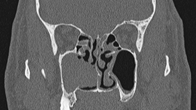

Based on the diagnosis, the patient underwent further surgical intervention. The pre-operative contrast enhanced CT scan revealed extensive residual mass on right maxillary sinus with minimal residual mass on the left maxillary antrum margin extending to the middle ethmoid through the surgical defect (Figure 2). Both frontoethmoidal recesses were filled with soft tissue mass while the rest of the sinuses were clear. Further surgery was carried out when right nasal cavity and antrum were found to be completely obliterated by polypoid tissue. Complete maxillary sinus clearance was achieved with endoscopic partial medial maxillectomy combined with canine fossa puncture. On the left side middle turbinate mucosa had several small polyps and left maxillary antrum macroscopically appeared clear. The histological examination of specimens from both nasal cavities revealed inverted papilloma with no epithelial dysplasia or malignancy. The patient remained under clinical surveillance and in year 2008 bilateral small nasal polyps were noted and further investigated by CT scan that demonstrated soft tissue mass filling right maxillary sinus and extended medially through surgical defect of medial maxillary sinus wall (Figure 3). The left sided nasal cavity did not reveal any suspicious features. He underwent right revision FESS and the histology showed IP in the specimen excised from the floor of right maxillary sinus.

Figure 3 Right sided IP recurrence (Year 2008).